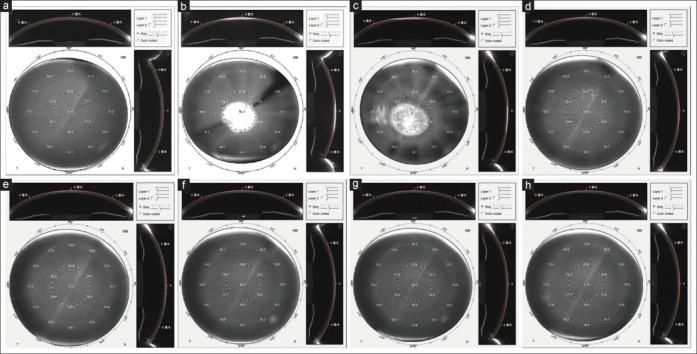

A case of severe diffuse lamellar keratitis after small-incision lenticule extraction operation.

Indian J Ophthalmol. 2024 Aug 1;72(8):1219-1223. doi: 10.4103/IJO.IJO_2974_23. Epub 2024 Jul 29.

https://cdn.ncbi.nlm.nih.gov/pmc/blobs/d316/11451777/a427438ca9e0/IJO-72-1219-g004.jpg

https://cdn.ncbi.nlm.nih.gov/pmc/blobs/d316/11451777/84d37d979e2c/IJO-72-1219-g001.jpg

https://cdn.ncbi.nlm.nih.gov/pmc/blobs/d316/11451777/b185e2c40e62/IJO-72-1219-g002.jpg

https://cdn.ncbi.nlm.nih.gov/pmc/blobs/d316/11451777/3c5cf51028d8/IJO-72-1219-g003.jpg